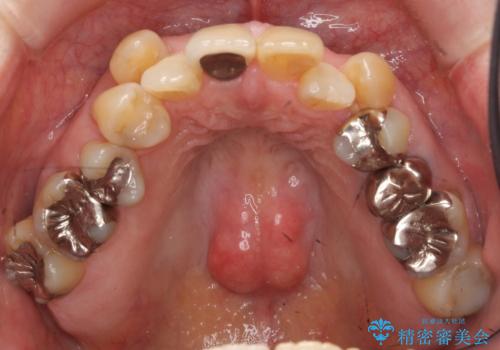

- 八重歯の矯正を希望されて来院。

歯は入りきらないため、通常の抜歯矯正を行いました。

歯がご年齢的に動きにくいため、被せ物のやり替えを含めて治療期間の短縮を図りました。

詰め物や被せ物のやり替えも併せて行っているため、治療期間を比較的短縮できました。